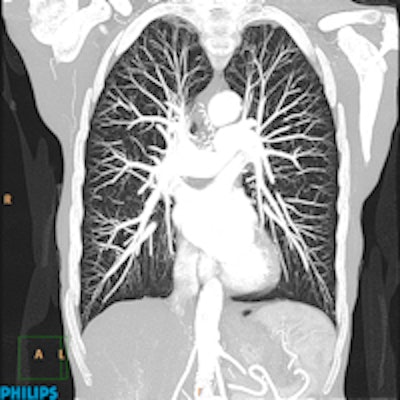

Ingenuity CT chest image processed with Philips' iDose4 iterative reconstruction algorithm at level 3 setting. Imaging parameters are 80 kVp, 91 mAs/slice, 32-cm coverage, 6.0-sec scan time, 1.7 mGy CTDIvol, 66.5 DLP (mGy-cm), and 0.9 mSv radiation dose.

Ingenuity Core is an entry-level 64-slice scanner that features 4 cm of patient coverage. At the middle of the Ingenuity line is Ingenuity Core128, a 128-slice scanner with a 33% improvement in x-axis spatial resolution. At the top of the line is Ingenuity CT, which is also a 128-slice scanner, but which features additional technologies such as Philips' iDose4 iterative reconstruction dose reduction algorithm and O-MAR (orthopedic metal artifact reduction) algorithm.

Philips is also highlighting clinical cases acquired with its iDose4 iterative reconstruction algorithm, which began shipping earlier this year. The studies include a chest case with an iDose4 level 3 image processing setting that resulted in 0.8 mSv of radiation dose at 80 kVp, and a case from China in which a brain study was acquired at a dose of 0.2 mSv. The company is touting a high-resolution inner ear case at a 1024 x 1024 matrix, which makes use of the ability of iDose4 to improve spatial resolution.